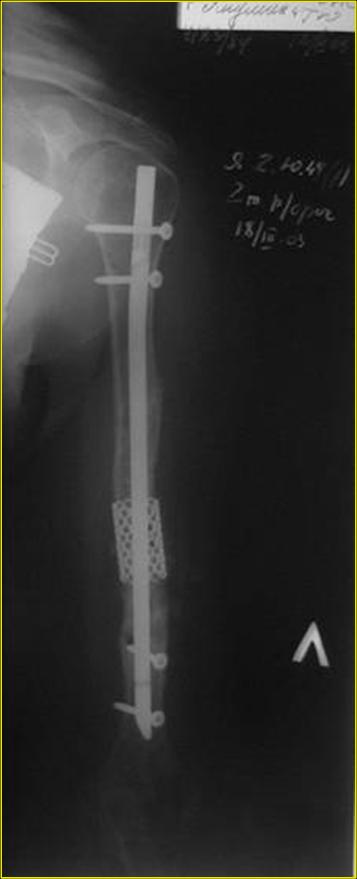

Типичная положительная ситуация для интрамедуллярного остеосинтеза с

использованием опорного металлокаркаса для компенсации дефекта.

Рентгеновская версия реконструкции. хронология:

после операции, 2 мес. после операции, через 1 год

Движения в полном объеме восстановлены к 2 мес. после операции. Если надо могу показать мультик. Сейчас уже прошло более 3 лет, больная не

показывается. Успехов ЛАФ.